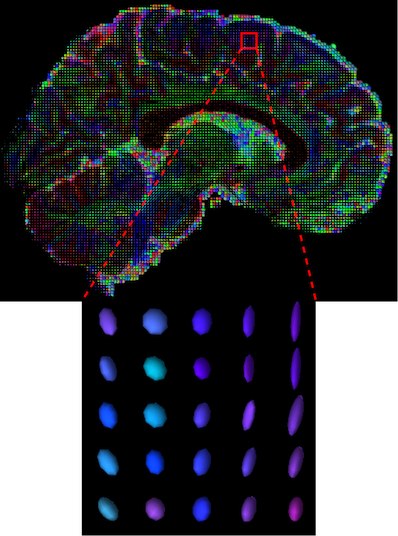

The visualization of inpainted results (showing the whole diffusion tensor for each voxel) generated from different models are demonstrated in Figure 3, where the tensor is represented in RGB coding that colours red, green and blue represent diffusion in the x, y, and z axes respectively. One typical example of reconstruction in the disrupted ROIs has been zoomed for visualization. Compared to the ground truth, TW-BAG is able to generate more distinct orientations following the original distribution and intensity across sagittal, coronal and axial views, which could demonstrate water diffusivity (denoted by eigenvalues of tensor model) more accurately. As indicated in Figure 4, the boundaries and textures of the FA map for TW-BAG are less blurry than the other competing models, validating the effectiveness of TW-BAG from a neuroscience perspective.